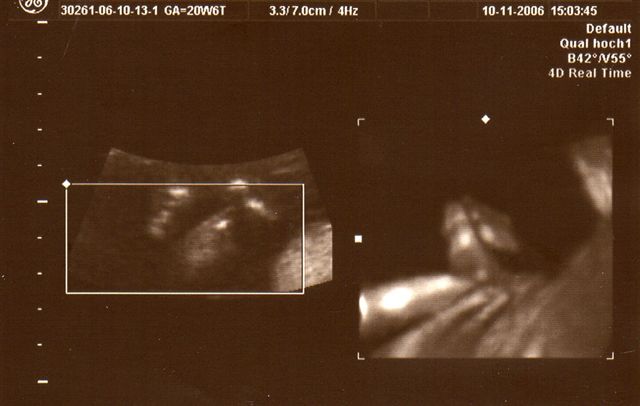

Wieder war ich beim "Partner-Doc". Dieses Mal stand das 2. Screening an, das um die 20. Schwangerschaftswoche herum gemacht wird. Wahrscheinlich hätte "mein" Doc seinen Partner eh gebeten dies durchzuführen, weil er das modernste Gerät hat. Ich hab dann so nebenbei erfahren, dass er wohl der einzige Doc in Düsseldorf ist neben dem Praenatal-Zentrum und der Diakonie, der dieses Ultraschallgerät besitzt. Was ich bzw. wir bei diesem großen Ultraschall zu sehen bekommen haben, war umwerfend und zugleich auch ein bißchen erschreckend - erschreckend nicht, weil mit Krümel etwas nicht in Ordnung ist, sondern weil man so unglaublich viel sehen kann, also positiv erschreckend. Jedenfalls ist alles in bester Ordnung. Jedes Organ ist da wo es hingehört und funktioniert so wie es funktionieren sollte, nichts fehlt. Krümel ist zudem zeitgerecht entwickelt, sehr beweglich und aktiv. Außerdem lag Krümel so günstig, dass der Doc zwischendurch auf 3D bzw. 4D-Realtime umschalten konnte und wir so faszinierende Bilder gesehen haben. Die schönsten hat er mit ausgedruckt. Eines davon seht ihr oben. Und einen Fuß hat er noch "eingefangen". Der Kopfumfang ist seit dem letzten Mal um fast 3 cm gewachsen und Krümel ist insgesamt geschätzt 16 cm lang, wobei dies ein reiner Schätzwert ist und sowohl nach unten, eher aber nach oben abweichen kann. Ich bin sooo glücklich dass alles in Ordnung ist. Lars´ Augen haben beim Anblick der "Fotos" geleuchtet und meinte: "Mami, ich hab das Baby sooooo lieb!"

So und nu zeig ich noch das "Fuß-Foto" :